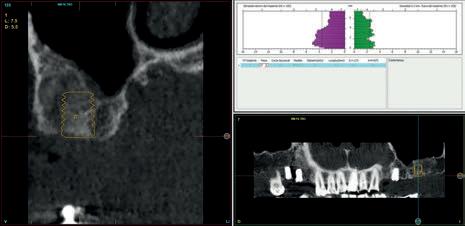

Para la planificación quirúrgica se realiza una tomografía dental computarizada de haz de cono (CBCT) que fue analizada posteriormente mediante un software específico (BTI-Scan III). En el CBCT se aprecia la presencia de diferentes lesiones periapicales asociadas a raíces remanentes. Por ello se planificó la extracción de las raíces dentales remanentes. Para la restauración oral, se planificó la restauración de piezas dentales con carillas de cerámica y los espacios edéntulos con prótesis fija sobre implantes.

Figura 3. La planificación quirúrgica de los implantes dentales. Los implantes en el primer cuadrante y el implante en la posición del primer molar superior izquierdo se realizarían en el primer acto quirúrgico junto con la extracción de raíces dentales remanentes. Mientras el implante en la posición del segundo molar superior izquierdo se realizaría dentro de 4 meses para conseguir la regeneración del defecto resultado de la extracción e inoculación de la lesión periapical.

Figura 4. La planificación quirúrgica de los implantes dentales en el maxilar inferior.